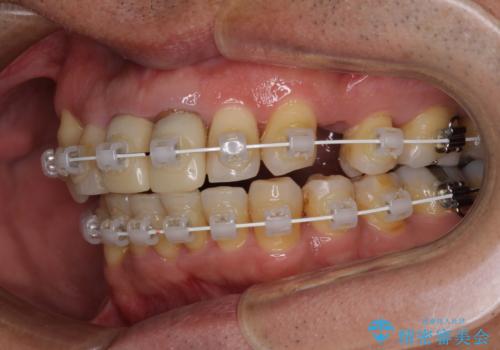

- 矯正装置

- 審美装置

上顎前歯の突出感と右上の八重歯を気にされていたので、上顎左右の第一小臼歯2本を抜歯し、ワイヤー装置にて矯正治療を行うこととしました。